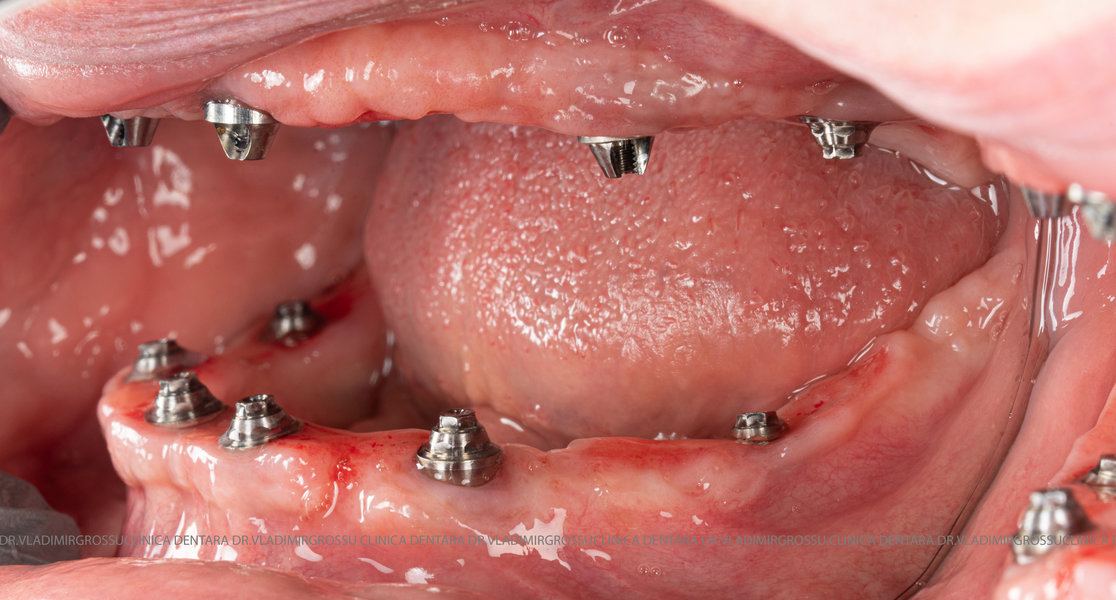

- Prima etapă constă în inserarea implanturilor și fixarea unei proteze provizorii, realizate de obicei din masă plastică frezată, ce este montată în a doua sau a treia zi postoperator. Suturile sunt îndepărtate după 5-7 zile.

- A doua etapă are loc la aproximativ 6 luni după intervenție, când se realizează proteza definitivă, care este fixată pe implanturi prin intermediul unor piese numite multiunit-uri. Această etapă presupune lucrul la nivelul multiunit-urilor, nu direct pe implanturi, reducând astfel riscul de complicații.

- Șase implanturi;

- Șase multiunit-uri, drepte sau angulate, în funcție de necesitățile protetice;

- Șase capete de confort;

- Șase abutment-uri provizorii montate pe multiunit-uri;